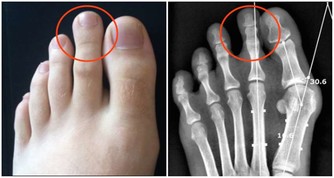

蓮藕蓮藕具有利尿作用,能促進體內廢物快速排出藉此淨化血液。